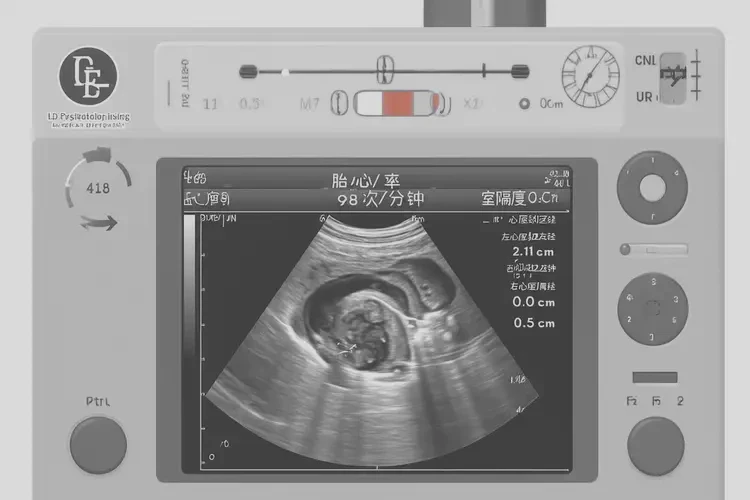

胎心98次/分钟在孕15周属于正常范围,宝宝可以继续妊娠。

胎心率是指胎儿心脏每分钟跳动的次数,是评估胎儿健康状况的重要指标之一。在孕15周时,胎儿的胎心率通常在140-170次/分钟之间。虽然98次/分钟略低于正常范围的下限,但并不意味着宝宝不能要。以下是详细的解释和建议: